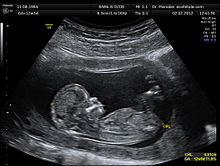

This Lammas dedication is seamlessly connected to the Imbolc Moment … the post-Winter Solstice welcoming of the new Light, the manifestation of the New Young One in all its sacred beauty. This New Young One is as connected to the Lammas Moment as the foetus is to the womb: it cannot Be without this darkness. To comprehend the simultaneous occurrence of these Moments of Creativity is to take in the whole Gestalt – Earth is doing both at the same time. As we take on a planetary mind in our times, holding the vision of EarthGaia as a whole being, we may sense more clearly the seamlessness of the Cosmos.